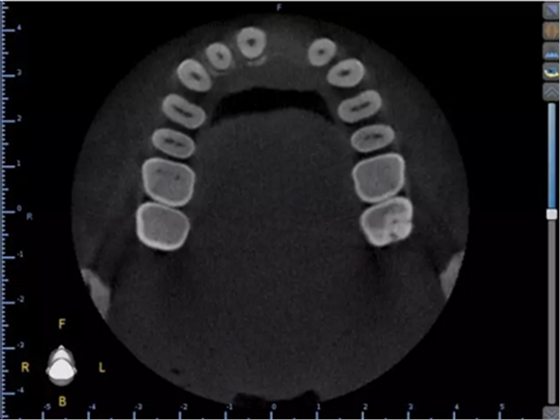

1.術(shù)前CT

2.術(shù)前植體設(shè)計(jì)

術(shù)后CT